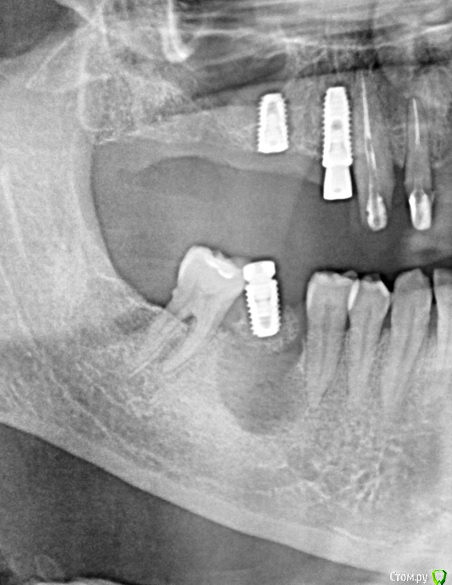

bullbull Опубликовано 15 октября, 2018 Поделиться Опубликовано 15 октября, 2018 Вот немного фэйла.Удаление, торк 45. Пациент пропадает на 1,5 месяца. Гигиена так себе. Работает в полях (директор совхоза или как-то так). Со слов - болит со дня установки. На вопрос: чего не звонил, не заходил? - Пожимает плечами. Извлёк руками без анестезии. Ссылка на комментарий